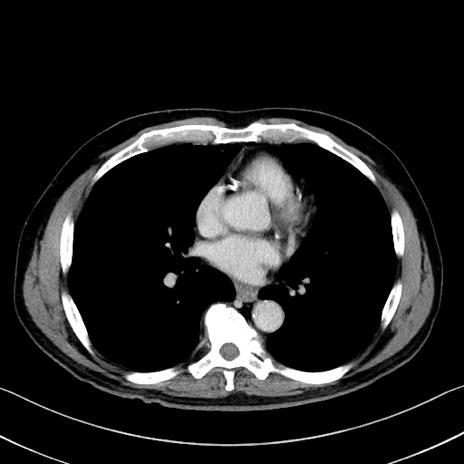

冠状断像

症例35(横断像)

【症例】70歳代 男性

【主訴】腹部膨満、嘔吐

【現病歴】昨日より腹部膨満感出現。本日増悪し、仙痛出現。嘔吐あり、受診。

【既往歴】糖尿病、胆摘後

【身体所見】BP 149/80mmHg、HR 74/min、BT 35.9℃、腹部:膨満、軟、圧痛なし。腸雑音減弱あり。上腹部正中切開瘢痕あり。

【データ】WBC 13500、CRP 1.72